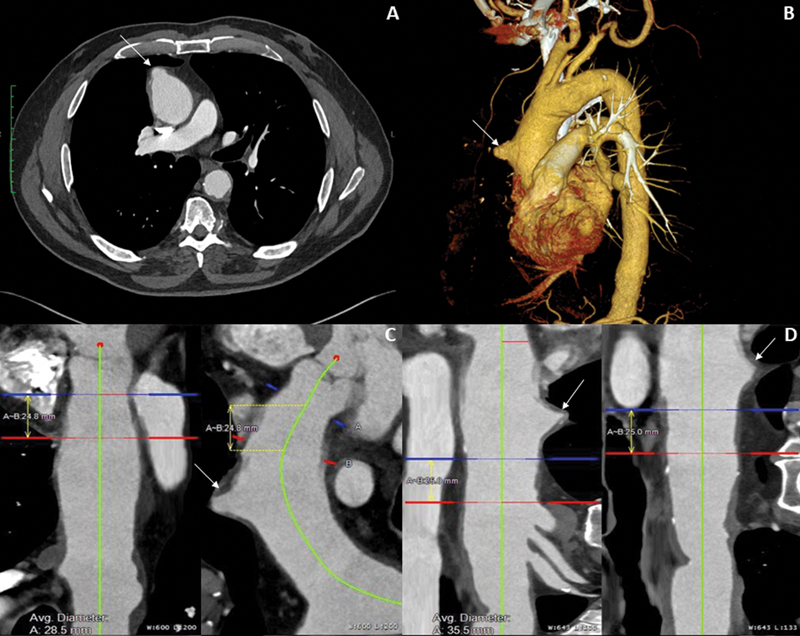

虽然开放手术是升主动脉病变的标准治疗方法,但血管内方法也是可行的选择。我们报告了一例患有 5.7 厘米升主动脉穿透性溃疡的 77 岁男性病例。考虑到患者的年龄和临床特征,他接受了 0 区胸腔内主动脉血管修补术。

Although open surgery is standard of care for ascending aortic pathology, endovascular approaches can be viable options. We report the case of a 77-year-old man with a 5.7-cm ascending aorta penetrating ulcer. Given his age and clinical profile, the patient underwent Zone 0 thoracic endovascular aortic repair.